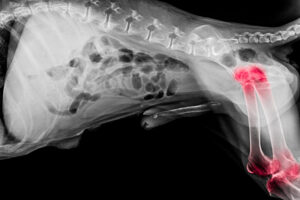

“Our Border Collie, Hannah, has hip dysplasia and our orthopedic vet Dr. Pam Nichols, at Animal Care Center K-9 Rehab Center, told us both hips were equally bad ….some of the worst she’d ever seen (hip dysplasia is one of the leading causes of arthritis in dogs). She was afraid Hannah would have to have both hips replaced to ensure a long active life, but suggested that we try stem cells first. Hannah used to use her front paws to pull herself up at times after a lot of running or play and the arthritis was very invasive. She was not making any extra trips upstairs and was unable to even stand on her hind legs.